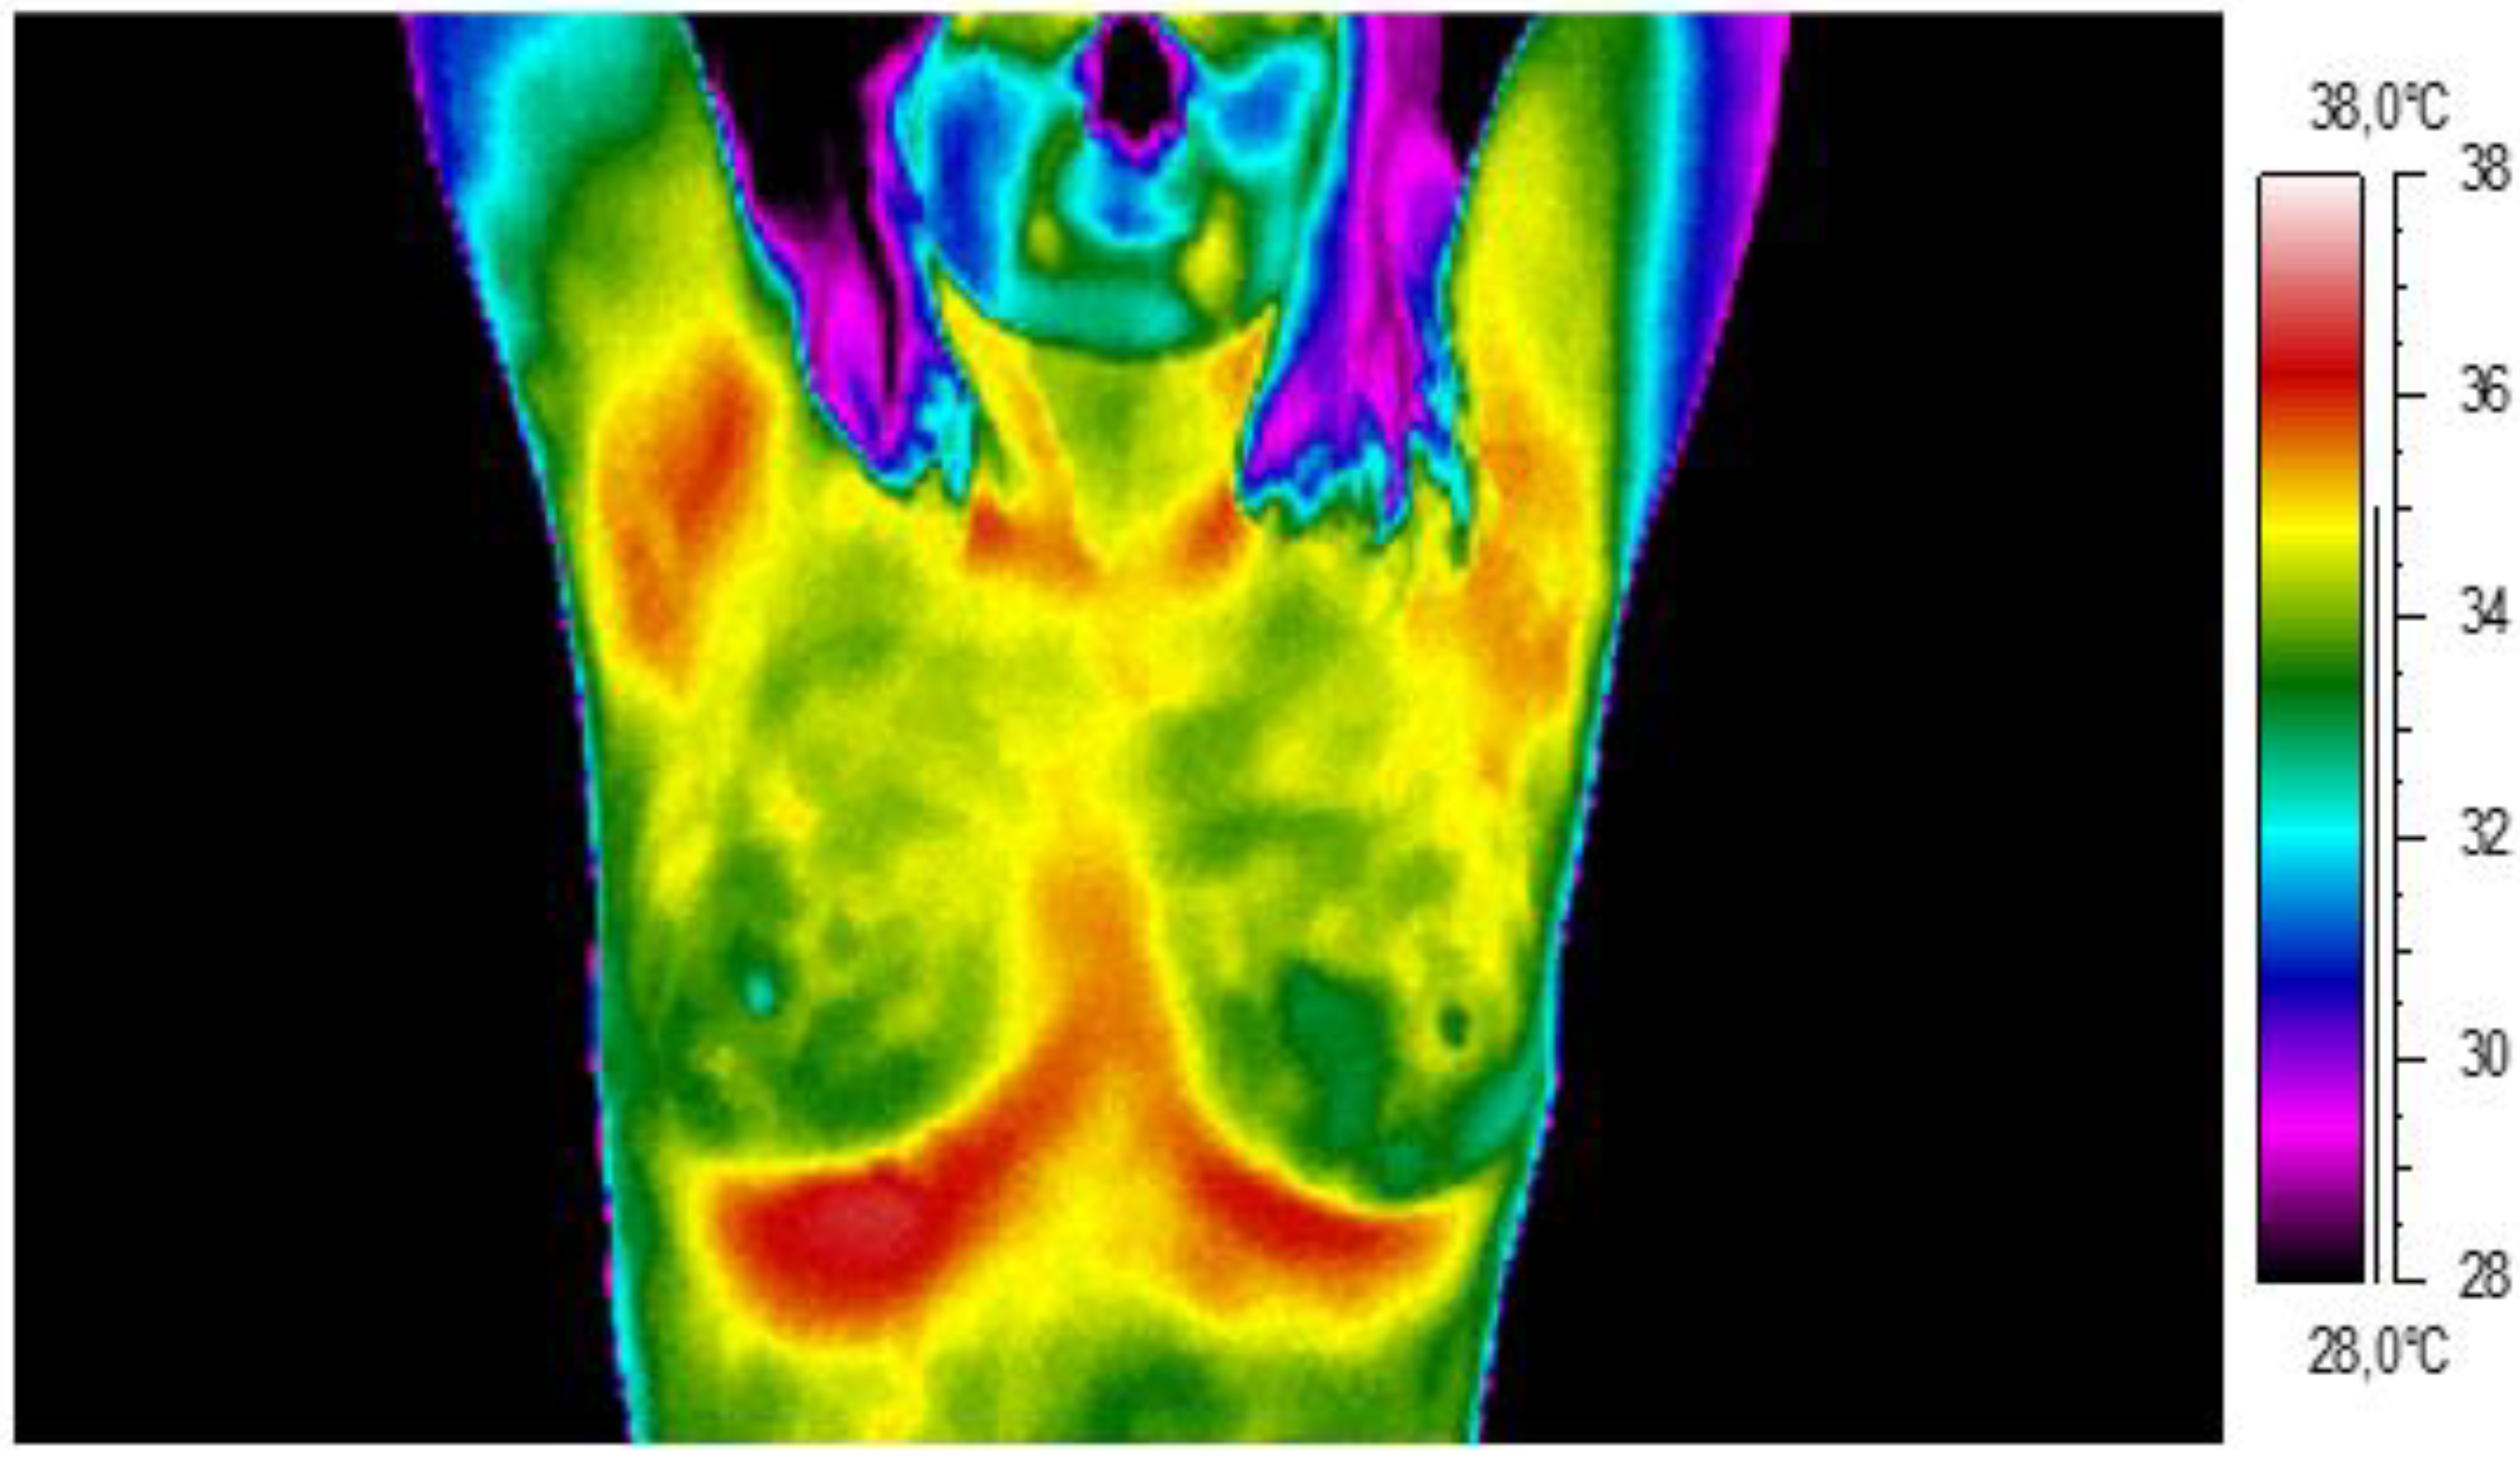

2. Materials and Methods

3. Results and Discussion